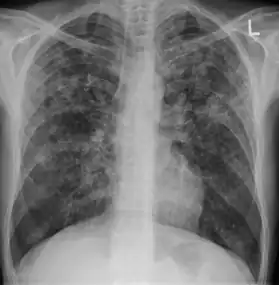

| Chest X ray showing miliary tuberculosis | |

Miliary tuberculosis is a form of tuberculosis that is characterized by a wide dissemination into the human body and by the tiny size of the lesions (1–5 mm). Its name comes from a distinctive pattern seen on a chest radiograph of many tiny spots distributed throughout the lung fields with the appearance similar to millet seeds—thus the term "miliary" tuberculosis. Miliary TB may infect any number of organs, including the lungs, liver, and spleen.[2] Miliary tuberculosis is present in about 2% of all reported cases of tuberculosis and accounts for up to 20% of all extra-pulmonary tuberculosis cases.[3]

A case of miliary tuberculosis in an 82-year-old woman:

X-ray, 13 days after onset, showing bilateral interstitial infiltrates

X-ray, 22 days after onset, showing extensive bilateral reticulo-nodular infiltrates